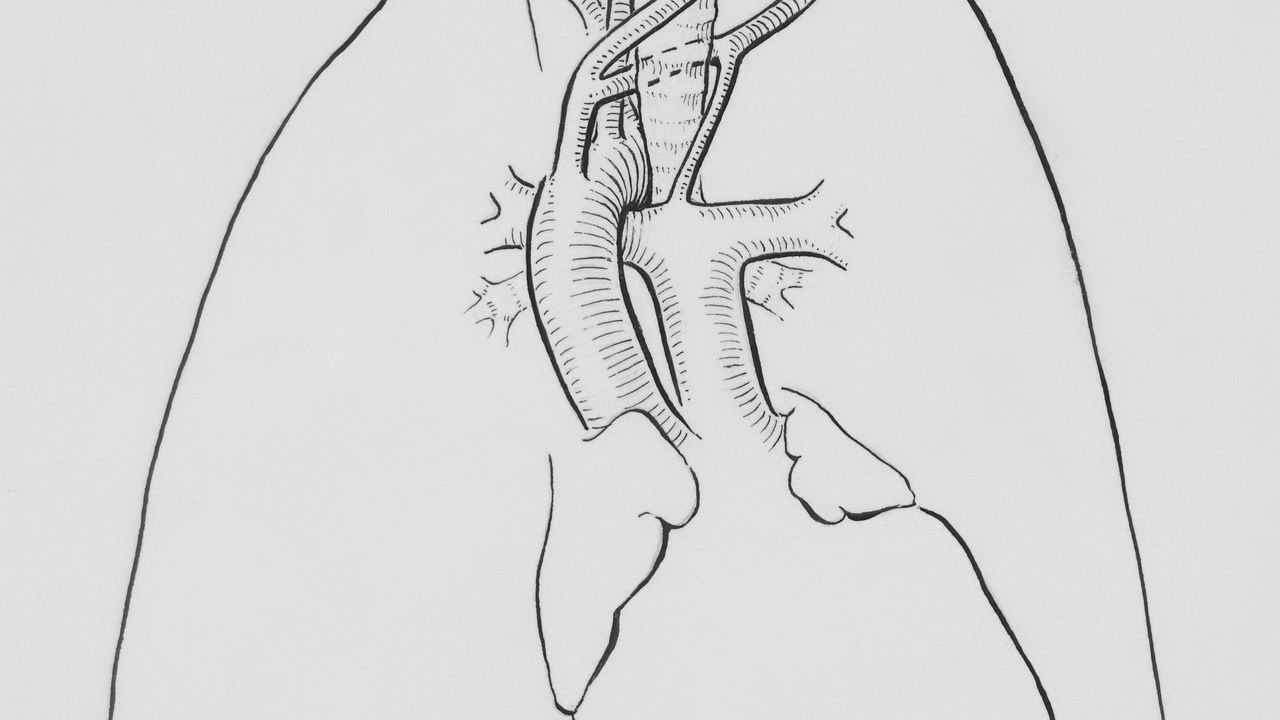

Anatomy and How the Lungs Work

The lungs are built for two complementary jobs: maximize the surface for gas exchange, and keep that surface clean and well perfused. Below you’ll find three related themes: the alveolar surface area that enables rapid oxygen uptake; the mucociliary clearance system that removes particles and microbes; and the lung’s specialized blood supply that makes diffusion extremely efficient. These basics set the stage for the numbered facts that follow.

2. The lungs are self-cleaning thanks to mucus and tiny cilia

The airways are lined with mucus that traps dust, pollen, and microbes, and with microscopic hair-like cilia that beat rhythmically to move that mucus upward toward the throat. Scientists call this the mucociliary escalator.

Cilia normally beat many times per second to clear particles; mucus is produced continuously and increases with irritation or infection. Cigarette smoke paralyzes cilia and thickens mucus, which explains why smokers develop chronic bronchitis and are more prone to lung infections.

3. Lungs have a specialized blood supply that maximizes gas exchange

Blood reaches the lungs through two systems: the pulmonary arteries carry deoxygenated blood from the right ventricle to the alveolar capillaries for gas exchange, while the bronchial circulation supplies airway tissues with nutrients.